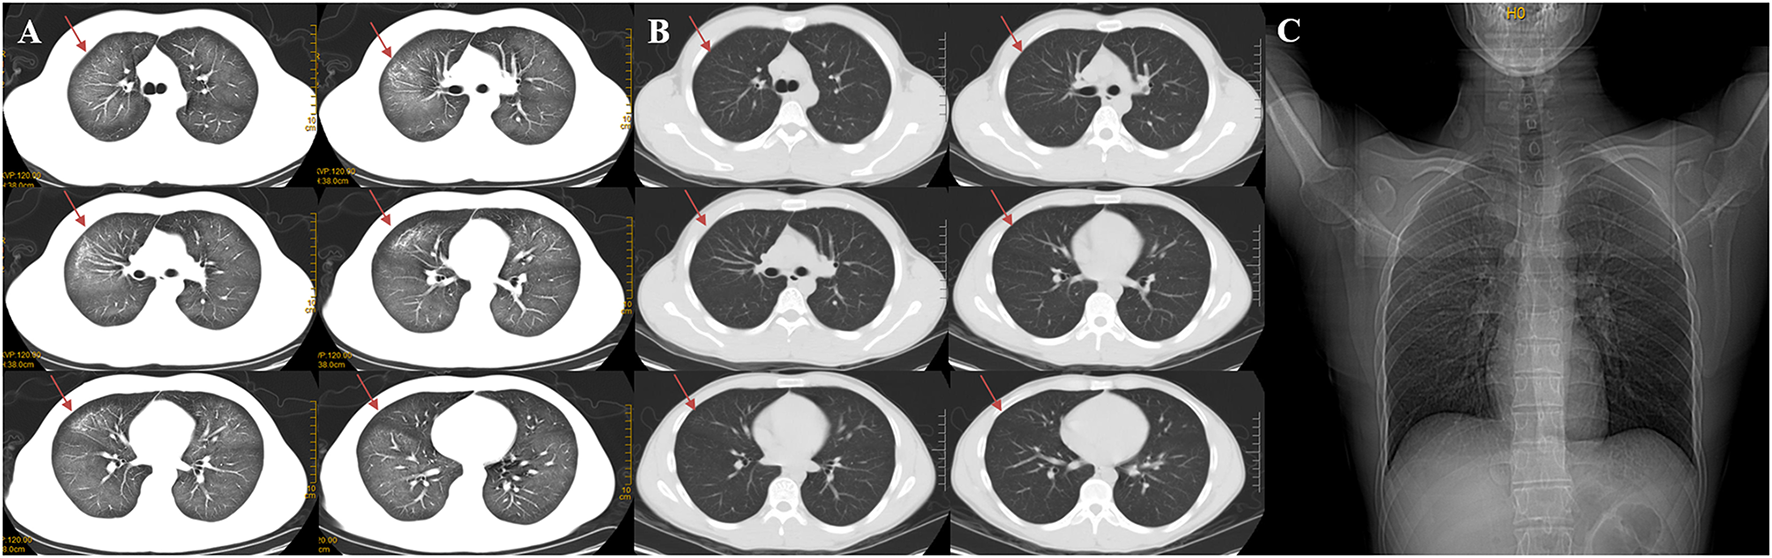

Figure 1

Changes of chest CT before (A) and after treatment (B), a CT contrast of marked absorption of the lesion after 3 days of treatment. Admission chest X-ray of the patient (C). (A) The chest CT scan demonstrated diffuse ground-glass opacity and infiltrative shadows. (B) After 3 days of using prednisone acetate, the chest HRCT revealed marked absorption of the pulmonary lesions. Red arrows show that the lesions in both lungs were absorbed. (C) Admission Chest X-ray of the patient demonstrated a decreased transparency in both lung field, and there was no signs of cardiomegaly and pleural effusion.

On admission, the routine blood test revealed total leucocyte count of 32.35 × 109/L, of which neutrophile granulocyte count of 29.25 × 109/L (90.4%), and procalcitonin (PCT) level of 8.66 ng/ml. C-reaction protein (CRP) level of 12.3 mg/L. There is no obvious abnormality of his blood serum chemistries and fibrin d-dimmer test, shown in Table 1. Blood gas analysis revealed PH 7.4, pO2 66 mmHg, pCO2 34 mmHg, HCO3− 20 mmol/L, BE −1 mmol/L. PaO2/FIO2 = 220 (Table 1). His lung CT scan images revealed diffuse ground glass and infiltrative shadows (Figure 1A). But there were no evidences of immunosuppression and pathogens with sputum culture and blood serum test, such as bacteria, fungus, EB virus, CMV virus and so on. His antinuclear and vasculitis antibodies tests were normal. Electrocardiogram showed sinus rhythm. Admission chest x-ray of the patient demonstrated a decreased transparency in both lung field, and there were no signs of cardiomegaly and pleural effusion (Figure 1C). We also used fluorescence bronchoscope to obtain bronchoalveolar alveolar lavage fluid (BALF) for mNGS. The results of the mNGS were compared with four microbial genome reference sequence databases downloaded from the National Center for Biotechnology Information, which included the whole genome sequence of 1,798 DNA viruses, 6,350 bacteria, and 1,604 fungi and 234 parasites genome sequences associated with human infection. The results of mNGS exhibited Dialister pneumosintes (sequence number 46) and Dialister invisus (sequence number 36) which can often isolate from the mouths of animals and even humans (13, 14). They are usually considered as conditional pathogens of immunocompromised individuals and rarely seen in immunocompetent patients, so these pathogens were considered to be contaminating or colonizing bacteria (Table 2).

Immediately on admission, based on the present and past history, age, clinical manifestations, physical examination and comprehensive auxiliary examinations, such as arterial blood gas analysis, a cardiogenic pulmonary edema was excluded and a preliminary diagnosis of mild ARDS was established. The patient was treated with moxifloxacin (400 mg given intravenously once a day), Cotrimoxazole (1,440 mg given orally every 8 h), oseltamivir (75 mg given orally twice a day), and terbutaline 1 mg (oxygen atomizing inhalation twice a day). We stopped anti-infective therapy after mNGS test, on account of lacking of etiological evidence. The recommendations from evidence-based medicine point out that a low dose of methylprednisolone 0.5–1 mg/kg body weight/d for mild ARDS (5). The total dosages of methylprednisolone were calculated based on the bodyweight of the patient (54 kg). And then the dosage of methylprednisolone (0.5 mg/kg body weight/d × 54 kg = 27 mg/d) was converted into the equivalent dosage of prednisone (27/4 × 5 = 33.75 mg/d). Subsequently, prednisone acetate (10 mg given orally three times a day) were started. The patient was afebrile and felt better after corticosteroid therapy. After 3 days of using prednisone acetate, the chest HRCT revealed a marked decrease of diffuse ground-glass opacity and infiltrative shadows (Figure 1B). The changes of neutrophil count, neutrophil proportion and white blood cell count had a continuously declining trend, which finally were close to normal. We decided to discharge the patient, and continued prednisone acetate for 10 days (10 mg given orally twice a day for 5 days and then 10 mg given orally once a day for 5 days). The patient treatment process is shown in Figure 2. During 12 weeks of follow-up, the patient was asymptomatic and was doing well. CT scans showed normal parenchyma of the lungs. Further follow-up observation is underway to research long term prognosis of ARDS patients involved in toxic inhalation.